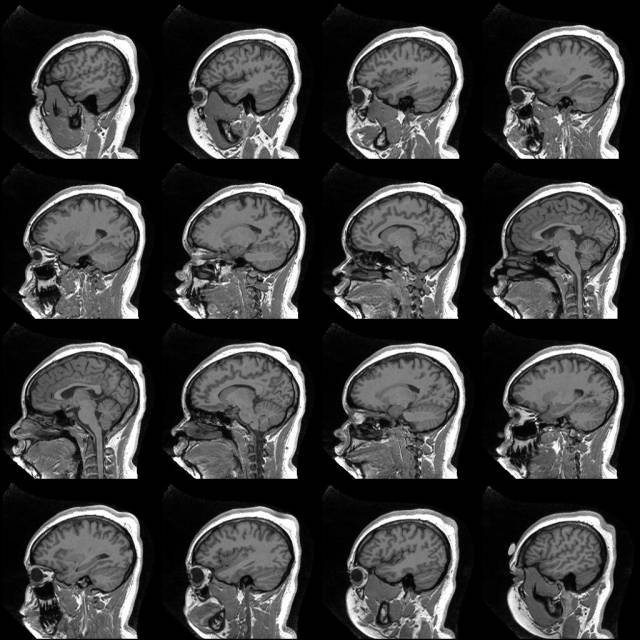

The images on this page (pre- and post-correction slices) have been produced with this procedure:

The resulting image then looked like this (on the right):